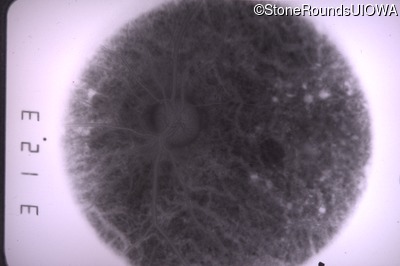

Goldmann Visual Field - Right - 20/20 sc

Exemplar